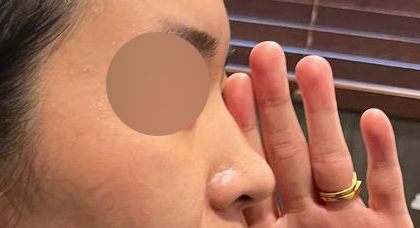

코성형 1개월차 찐 후기:)

1개월차 찐 후기 올려요 :)

지금 제 코는 만족스러우며 아직 한달지만

주마다 코 모양이 달라지는걸 느끼고 있습니다!

보는 사람마다 뭔가 달라졌는데? 뭐야 왜 점점 이뻐져?

이미지가 달라졌어! 이말만 오조오억번 듣는중입니다^_^